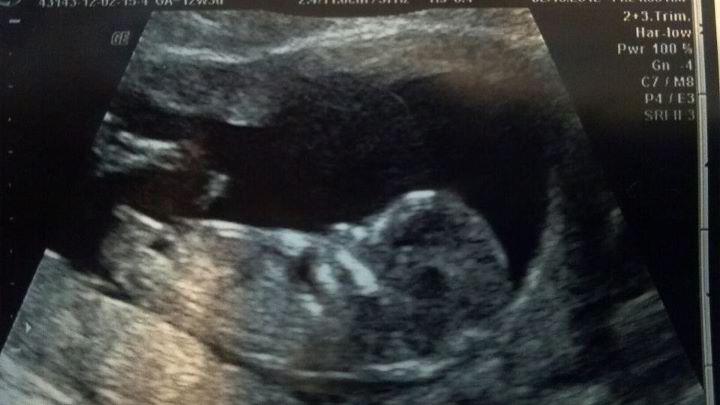

Looks like a girly nub

Looks like the placenta may be under the babies butt. But I am not to sure on that. Nub is girly.

Nub looks girlie.